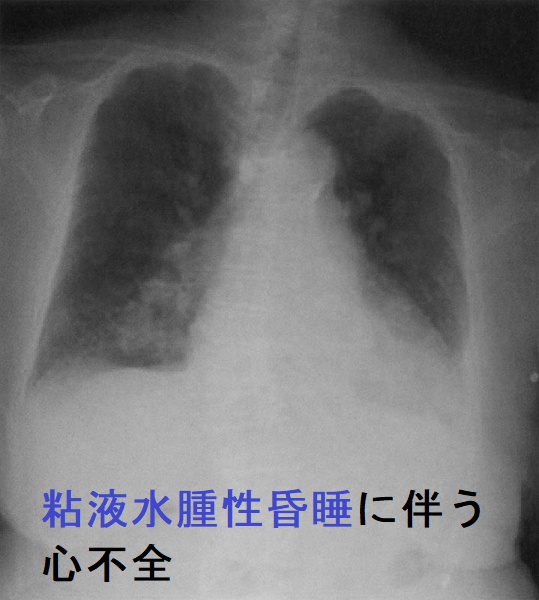

- 心不全

- 低ナトリウム(Na)血症・BNP高値